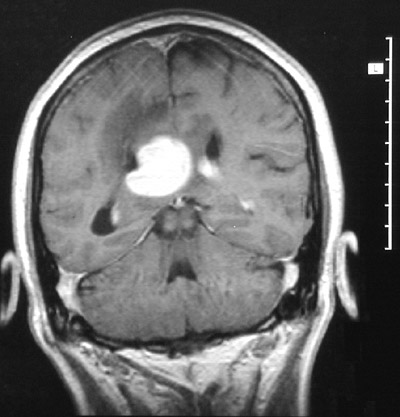

This MRI scan of the head in coronal view demonstrates an enhancing

periventricular mass

with prominent adjacent

vasogenic edema

. This is a non-Hodgkin's lymphoma.